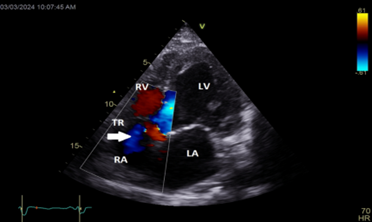

Color Doppler mapping of the tricuspid valve showed severe tricuspid regurgitation (TR) (Figure 5).

Figure 5: Apical 4 chambers view showing severe tricuspid regurgitation (white arrow).

LA=left atrium; LV=left ventricle; RA=right atrium; RV=right ventricle; TR=tricuspid regurgitation

Color Doppler mapping of the tricuspid valve showed a decrease in TR with only grade I tricuspid regurgitation noted after correction of hypocalcemia (Figure 9).

Figure 9: Apical 4 chambers view showing decrease of the tricuspid regurgitation severity (white arrow) after correction of hypocalcemia. LA=left atrium; LV=left ventricle; RA=right atrium; RV=right ventricle; TR=tricuspid regurgitation.